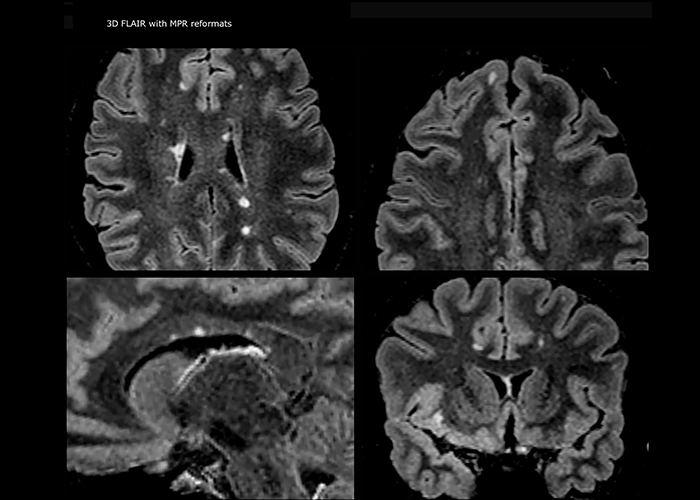

“Ingenia 3.0T provides us very good image quality with high SNR, even if we push the resolution. For example, in FLAIR images we may have an isotropic resolution of 0.9 mm. Ingenia allows us to use 3D T1 TSE with BrainView, which has a better sensitivity than 2D spin echo imaging[2] and 3D gradient echo imaging. Ingenia also provides highly reproducible exams, which is important in MS imaging so that follow-up exams at different time points are done the same way.”

Imaging MS in brain

For MS imaging in the brain, Dr. Savatovsky uses 3D FLAIR as the basic sequence to visualize the lesions and assess the situation and lesion load. “We count the lesions in each location to determine if the criteria of the disease are fulfilled. We use a T2-weighted sequence because our neurologists are used to it. We compare the lesion load on FLAIR with a 3D T1 post-contrast sequence to help us determine whether lesions are old or new. We typically administer the contrast before the patient enters the machine because it shortens the examination time and allows to visualize active lesions that tend to be more visible after several minutes. When a differential diagnosis is difficult, we add sequences such as susceptibility imaging, because some focal MS lesions have a small vein in the center[3].”